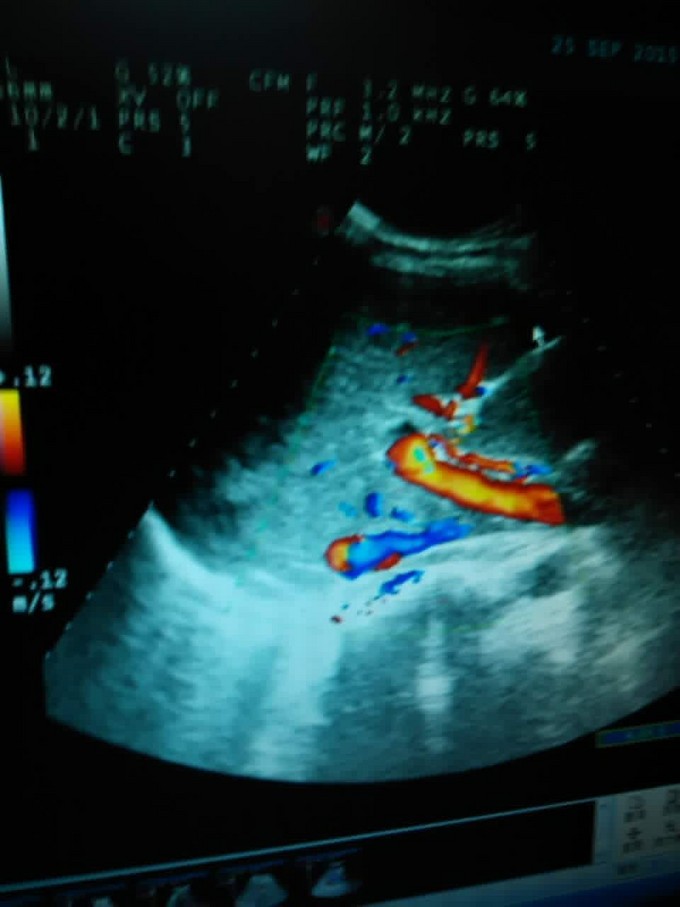

患者诊断胆漏明确,可根据影像学分析,行保守治疗。限期行经十二指肠鼻胆管引流。

肝胆手术后胆漏发生的原因与肝胆手术方式直接相关,胆漏出现在分析原因时应采纳手术者的分析意见,结合必要的影像学资料或再次手术证实。 原则上胆汁通畅无腹膜炎者咳保守治疗;对引流量大伴有局限性腹膜炎的可同时行腹腔及胆道双引流。本例患者胆漏出现的症状较轻,而且没胆道梗阻或腹膜炎症状,影像学明确下仍可采取保守治疗,可经十二指肠镜放置鼻胆管引流。